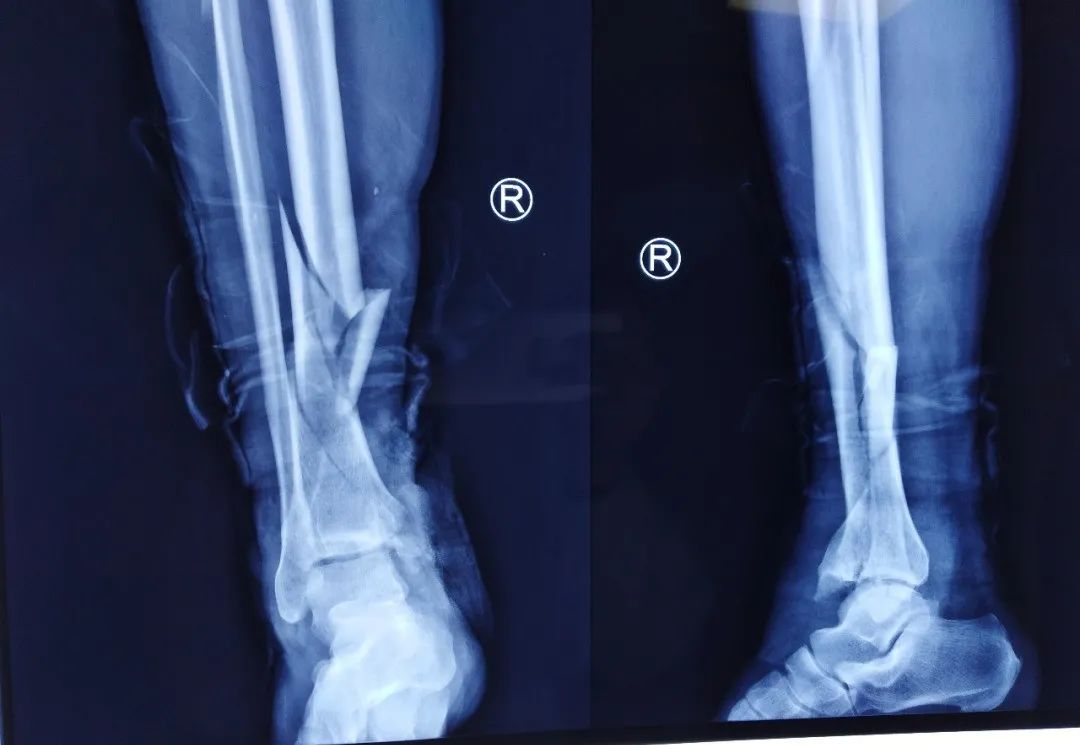

术前平片

该患者车祸伤入院,入院查体可见右内踝皮肤缺损面积约5cm*10cm,右足背部皮肤脱套伤,内踝缺如。患者既往高血压、糖尿病,一直服用利血平及阿司匹林。利血平一般建议停用2周,阿司匹林建议停用1周方能进行麻醉。不手术,患者开放性损伤,持续流血状态,失血过多会发生生命危险。手术的话,服用利血平有术中发生血压不能维持,呼吸心跳骤停的风险。麻醉医师团队及创伤骨科医师团队面临双重风险,两害相权取其轻。患者开放性损伤,时间就是生命。面对困难,勇于承担,经患者及家属同意,第一时间进行了第一次清创+外固定支架固定+VSD负压引流手术。后续又进行了第二次清创+外固定支架调整+抗生素骨水泥链植入+克氏针固定踝关节骨折+VSD负压引流手术。第三次清创+骨折复位螺钉内固定+内踝重建+Ilizarov环形外固定固定+VSD负压引流手术。手术均进行顺利。